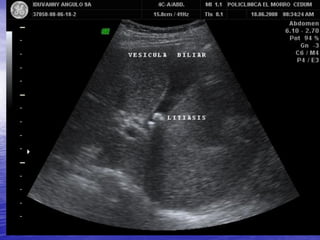

PATOLOGIA BILIAR

LITIASIS VESICULAR

SOBREDISTENSION DE LA

VESICULA BILIAR

• AYUNO PROLONGADO

• OBSTRUCCION DE LA VESICULA

O DEL ARBOL BILIAR.

OBSTRUCCION POR LITIASIS